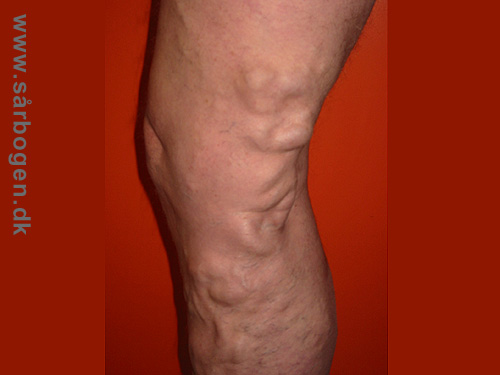

Magnavaricer